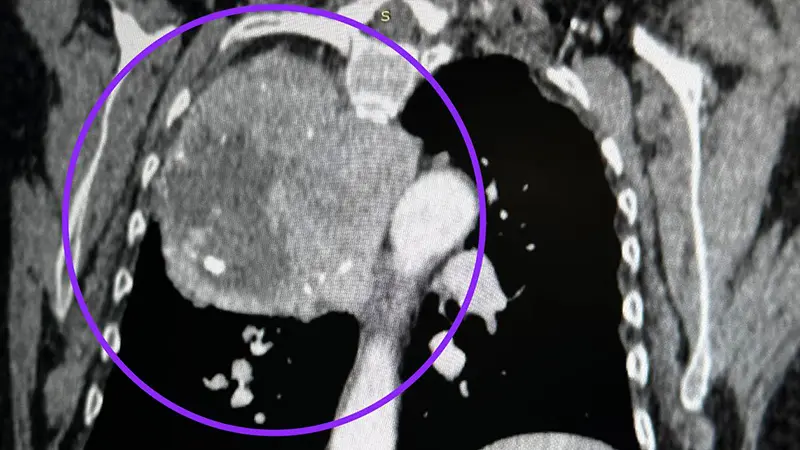

В этот же раз опухоль выросла из нижнего полюса щитовидной железы и заняла треть грудной клетки. На помощь пришли торакальные хирурги РКБ Татарстана. Они подчеркнули, что впервые на практике встретились с такой опухолью. Хирурги удалили её через разрез между ребер примерно за 3 часа.